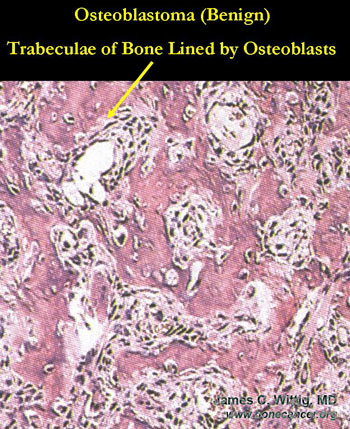

Osteoblastoma (benign bone-forming tumor) vs. Osteosarcoma

- Osteoblastoma usually geographic, benign appearing lesion on x-ray

- Osteosarcoma usually permeative on x-ray

- Osteoblastomas have thick, irregular trabeculae of osteoid and woven bone with osteoblastic rimming

- Trabeculae of osteoblastoma are separated by intervening stroma with capillaries and osteoclasts/giant cells

- Osteosarcomas infiltrate surrounding lamellar bone, whereas osteoblastomas grow with a pushing margin. There is a sharp cut off between the osteoblastoma and normal bone at the periphery of the osteoblastoma. Osteoblastomas do not permeate the surrounding lamellar bone.

- There is no cartilage in an osteoblastoma, unless it has fractured the bone or the lesion has been biopsied